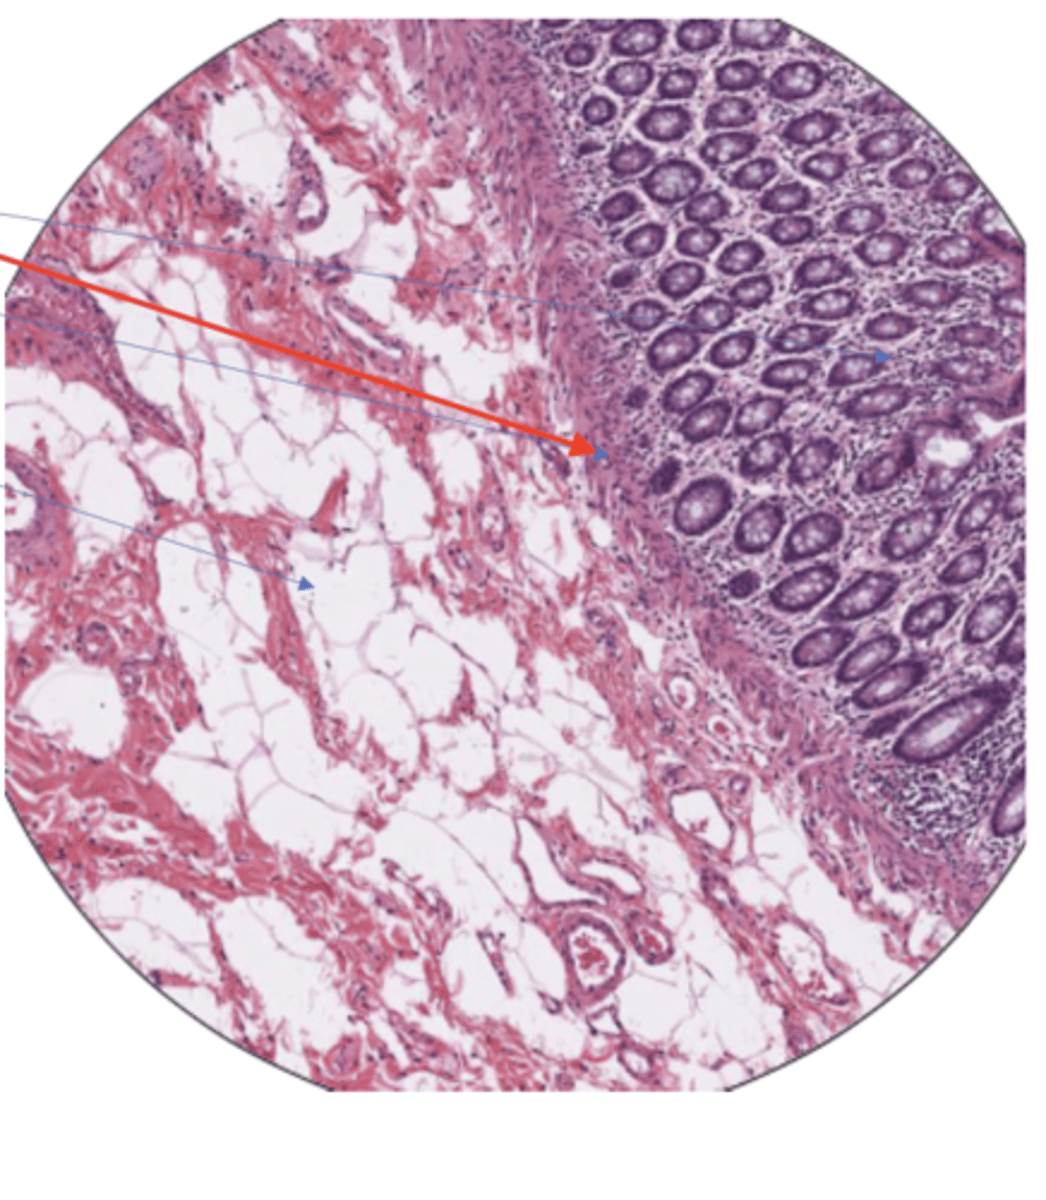

SI muscularis mucosa

SI mucosa

SI serosa

SI submucosa

SI duodenal glands

SI mucosa layer (100)

SI mucosa layer (400)